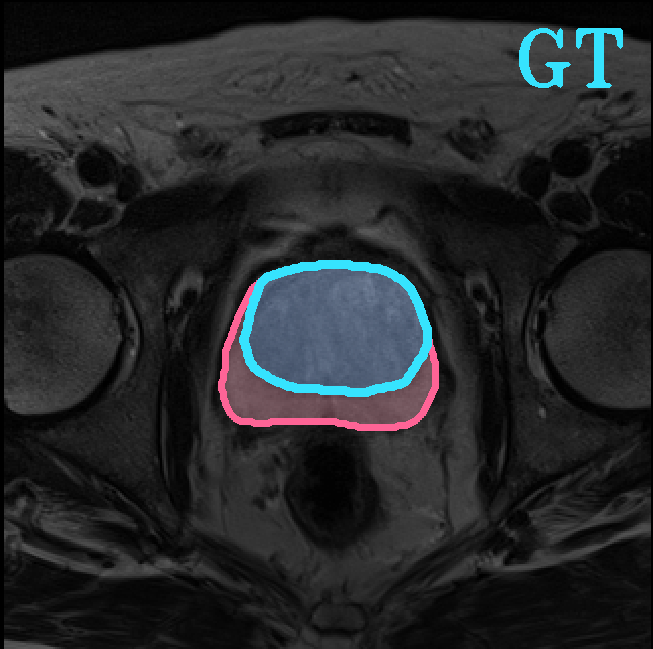

TransFuse is evaluated on both 2D and 3D datasets to demonstrate the effectiveness. As different medical image segmentation tasks serve different diagnosis or operative purposes, we follow the commonly used evaluation metrics for each of the segmentation tasks to quantitatively analyze the results. Selected visualization results of TransFuse-S are shown in Fig. 2.

Results of Prostate Segmentation. We compare TransFuse-S with nnU-Net [12], which ranked 1st in the prostate segmentation challenge [22]. We follow the same preprocessing, training as well as evaluation schemes of the publicly available nnU-Net framework333https://github.com/MIC-DKFZ/nnUNet and report the 5-fold cross validation results in Tab. 6. We can find that TransFuse-S surpasses nnUNet-2d by a large margin (+4.2%) in terms of the mean dice score. Compared to nnUNet-3d, TransFuse-S not only achieves better performance, but also reduces the number of parameters by 41% and increases the throughput by 50% (on GTX1080).

| Prostate Segmentation | |||

|

|

|

|